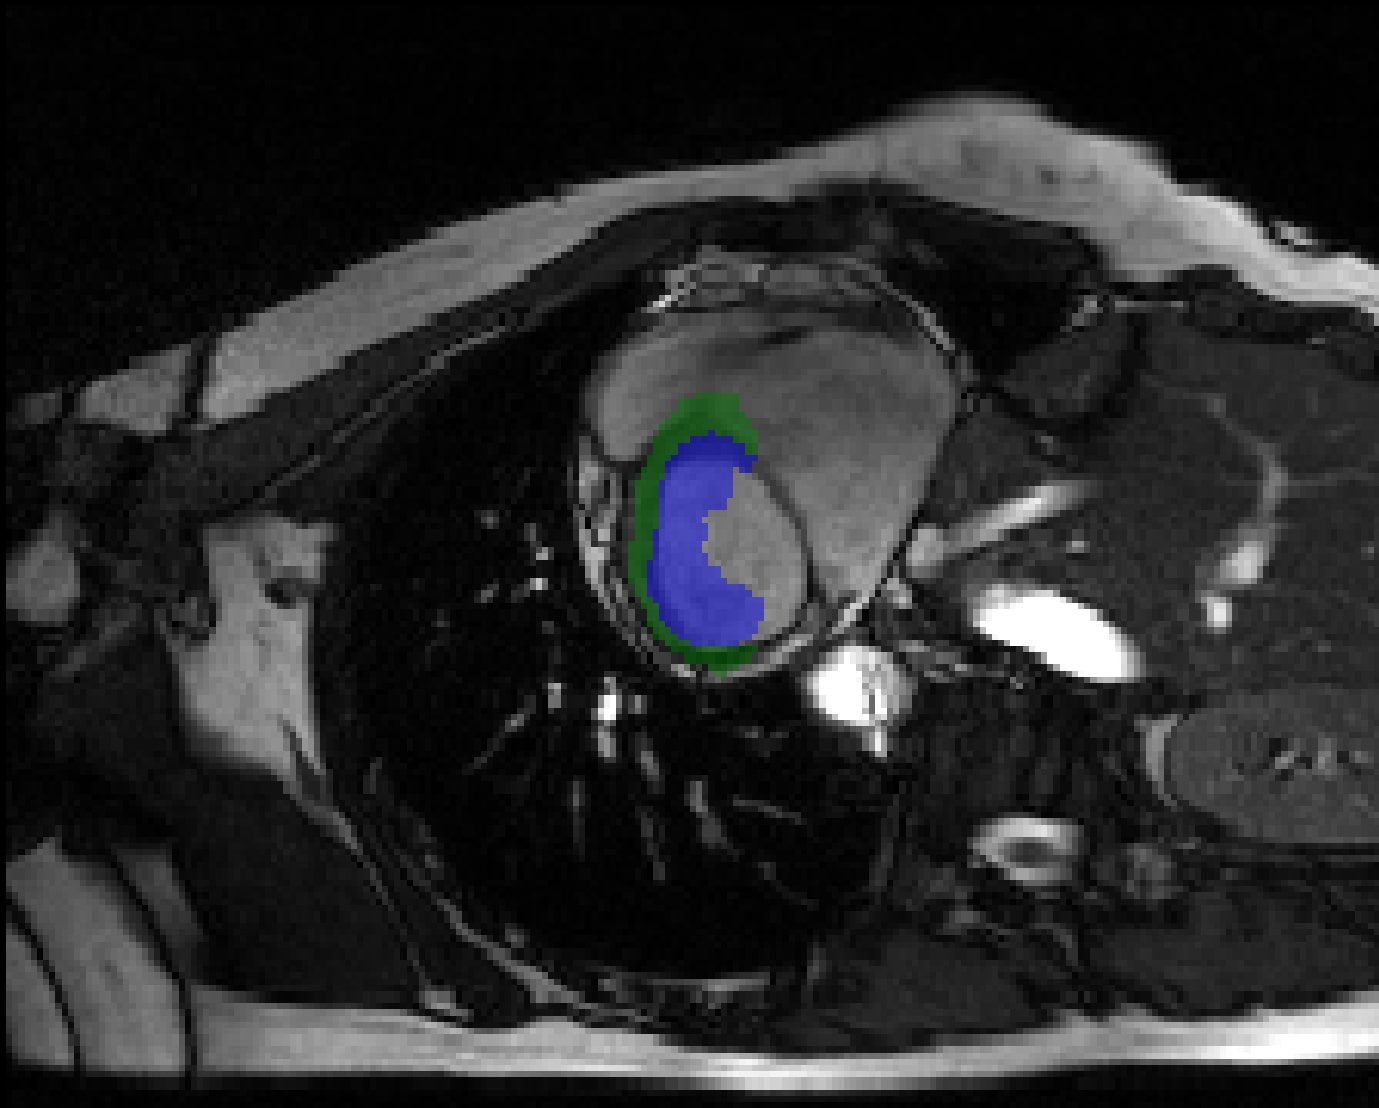

Automated Cardiac Diagnosis Challenge (ACDC) Bernard et al. (2018): The ACDC dataset, specifically designed to advance 3D cardiac image segmentation, consists of a collection of cine MRI images from a diverse group of 100 patients. This dataset is crucial for the advancement of advanced 3D segmentation algorithms, specifically in the accurate delineation of three major cardiac anatomical structures: the left ventricle (LV), the right ventricle (RV), and the myocardium (Myo). Each scan in this dataset provides intricate visual representations of these structures, allowing for extremely precise segmentation. The MRI scans vary in spatial resolution, typically ranging from 1.37 to 1.68 mm² per pixel. Furthermore, the dataset consists primarily of images with a slice thickness of 5 mm, while there are some occurrences with a slice thickness of 8 mm thickness. Occasionally, there is a 5 mm gap between slices. The variance in the thickness and the gaps between slices present specific obstacles for segmentation algorithms. These challenges require the use of strong approaches that can successfully handle these differences.

In terms of preprocessing, the method adheres to the protocols established in Chen et al. (2023); Shaker et al. (2022), involving the random cropping of images to dimensions of 160 x 160 x 16 and using sliding windows for the inference. The patient dataset is partitioned into separate subsets for the purpose of model training and evaluation. Specifically, 70 patients are assigned for training, 10 for validation, and 20 for testing. This allocation ensures a thorough evaluation of the segmentation models that are generated using the ACDC dataset.

Automated Cardiac Diagnosis Challenge (ACDC): Figure˜4 presents a qualitative, two-dimensional evaluation of cardiac segmentation across several state-of-the-art models within the Automated Cardiac Diagnosis Challenge (ACDC) dataset. This visual assessment spans across three distinct patient cases, each represented by a different row of images, to illuminate the comparative performance of each model in segmenting the left ventricle (LV), myocardium (Myo), and right ventricle (RV). In the first patient, depicted in the top row, there is a noticeable challenge for the models in segmenting the RV, with LHU-Net demonstrating a partial success in capturing some aspects of this anatomical structure. TC-CoNet and UNETR, in particular, exhibit difficulties in accurately delineating the Myo and LV, as evidenced by the deviations from the ground truth. Moving to the second patient, shown in the middle row, the absence of the RV in the slice poses a test of the models’ specificity, where false positives are a concern. In this instance, LHU-Net shows commendable restraint, avoiding the overprediction seen in nnFormer and TC-CoNet, which falsely identify a substantial RV presence. Meanwhile, all models perform well on the Myo and LV, indicating their effectiveness in these regions under less challenging circumstances. The third patient’s imagery, the bottom row, provides a scenario where LHU-Net’s segmentation closely aligns with the ground truth, effectively capturing all relevant cardiac structures. Conversely, nnFormer and TC-CoNet tend towards over-segmentation of the RV, and UNETR presents with under-segmentation, highlighting a potential limitation in their segmentation algorithms. In conclusion, the visualization suggests that LHU-Net possesses superior robustness and precision in cardiac structure segmentation, outperforming the other models under various conditions. This robustness is particularly notable in instances of potential false positives or challenging RV delineation, where LHU-Net maintains high fidelity to the ground truth.